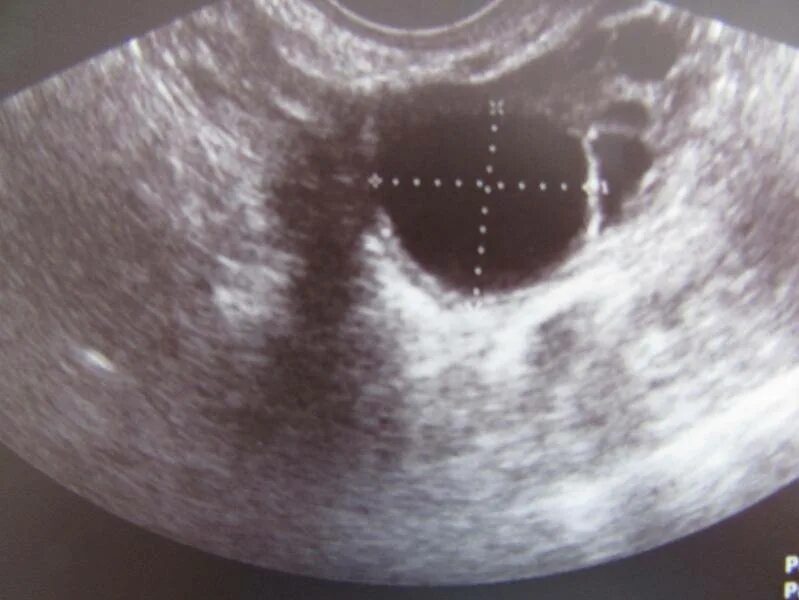

Эндометрий 9 мм